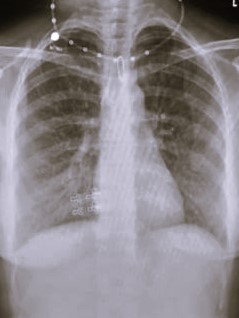

| 338 | IGGMC, Nagpur, Nagpur | P2 | 29-4134 | Rupesh Dongse | Consent taken on Paper | 43 Yrs. |

Provisional Diag : Consolidation

Final Diag : Bilateral Consolidation Community Acquired Pneumonia With Type 1 Respi Failure In Cronic Alcoholic |

Non-TB Case (Confirmed) | Bilateral Consolidation | Abnormality visible on x-ray |